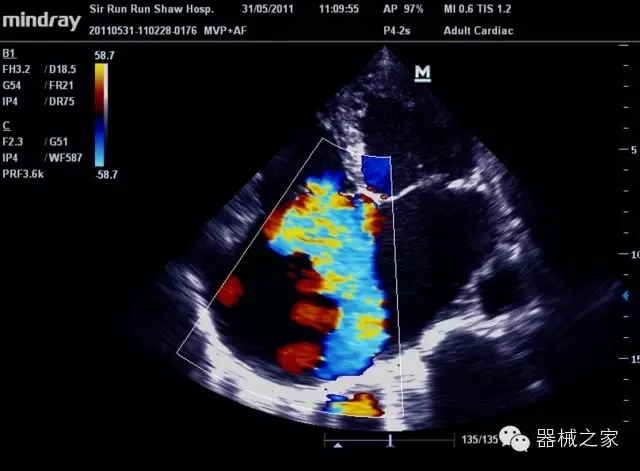

臨床圖片賞析

產(chǎn)品特點(diǎn)

·裝載有采用Multi-Core多核處理的非嵌入式平臺,成像效率大大提高,并且能夠給用戶帶來高速、多任務(wù)并行信號處理體驗(yàn);

·優(yōu)秀的圖像效果、強(qiáng)大的功能體驗(yàn)、豐富的探頭選擇、合理的便攜式設(shè)計(jì),全中文顯示及病人管理界面,使得M7在任何場合、任何時候都能快速響應(yīng)更好的心血管、腹部、婦產(chǎn)、小器官等常規(guī)超聲檢查以及肌骨、神經(jīng)、顱腦、術(shù)中等新興領(lǐng)域的使用需求;

8倍波束并行處理系統(tǒng)

·在便攜式緊湊平臺上采用更多倍波束并行接收信號處理模式,無論二維還是彩色血流圖像狀態(tài)下,擁有更靈敏的回波頻移捕獲能力,大大提高時間分辨率,尤其使得心血管表現(xiàn)更為突出;